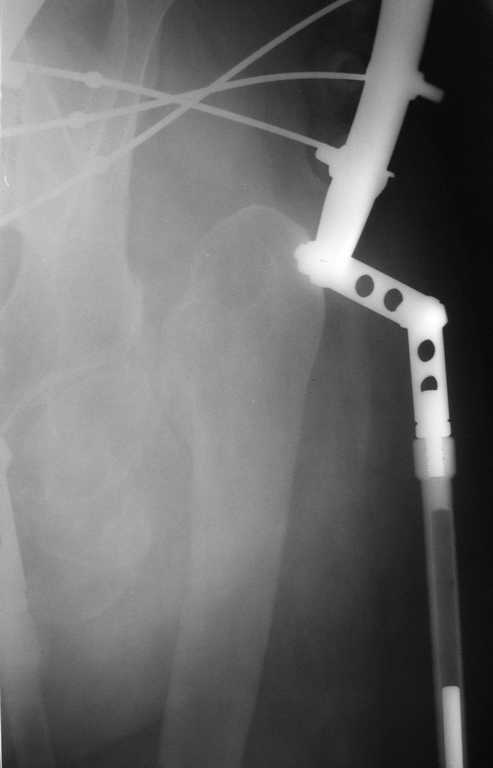

Приведу клинический пример несколько схожий с Вашим. Пациент 56 лет, 18 лет назад получил перелом шейки бедренной кости. Полноценного лечения не получил и остался с неопорным бедром. Укорочение было в районе 6-7 см. Первым этапом после миотомии приводящих мышц в теч. 2-х недель низвели бедро аппаратом Илизарова, далее сняв аппарат установили эндопротез гибридной фиксации (выраженный остепороз впадины ввиду отсутствия нагрузки). К сожалению, в процессе установки ножки эндопротеза произошёл перипротезный перелом медиальной стенки и профилактически мы наложили серкляжные швы. Контроль через 12 месяцев -укорочения нет, функция нормальная. Оперирован в 2005 году. с 2006 года к нам не обращался. АИФ